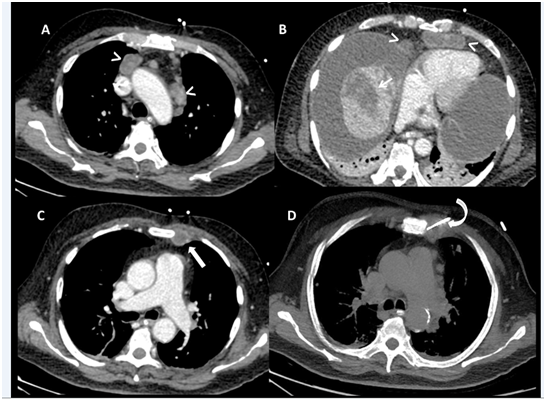

A sixty five-year-old male, diagnosed as a case of non-alcoholic steato-hepatitis related compensated chronic liver disease since one year, presented to us with complaints of progressive non cholestatic jaundice without prodrome for a period of 20 days. This was followed by painless abdominal distension and decreased urine output. The patient subsequently developed altered sensorium in a period of two days associated with excessive drowsiness along with high grade fever. He was teetotaller with history of type II diabetes since 12 years and had no other co-morbidities .There was no history of blood transfusions, alternative medicine intake. He was intubated outside and shifted to us on ventilator and inotropic support. Labs results showed haemoglobin 9.6 g/dL, white blood cell 27880/mm3 ,platelet 98000/mm3, BUN 93 mg/dL ,serum creatinine 4.01mg/dL ,severe metabolic acidosis with arterial lactate of 4.5 mmol/L. Liver function tests showed AST 40 U/L, ALT 32 U/L, alkaline phosphatase 129 U/L, GGT 45 U/L and bilirubin of 1.18 mg/dl. PT INR was 4.5 with very low fibrinogen. Acute viral markers (hepatitis A & E) and hepatitis B and C serology were negative, malaria antigen and leptospira IgM were nonreactive. Autoimmune markers were negative. Ultrasonography(USG) showed features of liver cirrhosis with portal hypertension. It also showed ill-marginated ill-defined subtle hypoechoic lesion in superior segment of right lobe with hypoechoic thrombus in right hepatic vein protruding into the inferior vena cava (Patients had been regularly following and his USG 3 months ago did not show any SOL). Ascitic fluid white cell count (842 cells/dL) with 72% neutrophils suggested spontaneous bacterial peritonitis. The α-fetoprotein level was 82 ng/mL. CA 19-9 and CEA were normal. Continuous renorenal replacement was initiated along with aggressive medical management for metabolic acidosis and hemodynamic instability. Contrast CT scan confirmed liver cirrhosis, gross ascites and splenomegaly (Figure 1) it also revealed a hypo-dense, ill-marginated, non-enhancing, sub-capsular mass in segment VII and VIII with non-enhancing, occlusive skip thrombi in the right hepatic vein protruding into IVC, occlusive thrombus of the right and main portal veins protruding into the left portal vein and retro-pancreatic splenic vein. Multiple enlarged necrotic pre-vascular, anterior peridiaphragmatic and pericardial lymph-nodes were also seen (Figure 2). In view of coagulopathy ,hemodynamic instability and cirrhosis it was decided to do the internal mammary lymph node after TEG based correction of coagulopathy . It showed (Figure 3) cells with biphasic neoplasm with epithelioid and spindle cells, marked nuclear pleomorphism with giant and bizarre nuclei and a high Ki-67 index. IHC showed strong coexpression of PanCK and Vimentin and was negative for LCA, CK7, CK20, TTF1, Hep Par-1, Glypican 3, p40. These features were suggestive metastatic PHSC. Meanwhile patient’s condition rapidly worsened over period of 5 days with development of multi organ failure. He eventually succumbed on the seventh day of hospital stay.

Figure 1 Contrast CT scan confirmed liver cirrhosis, gross ascites and splenomegaly.